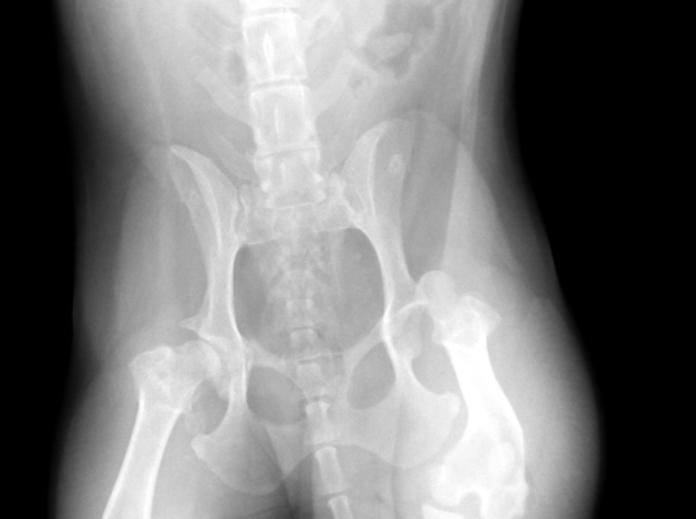

股関節脱臼

股関節は骨盤と大腿骨をつなげる関節です。大腿骨頭という円形の骨端が骨盤の寛骨臼という凹みにぴったり収まって機能する関節です。

この股関節が転倒や転落、交通事故など大きな力が加わることにより外れる状態を股関節脱臼と言います。犬の場合犬種によって元々外れやすい(関節が緩い)ことがあります。治療は外れたものを戻すことが基本となり様々な治療がありますが、再発やその都度強い痛みや跛行・接地不全を起こすこともあり骨頭を切除し歩様を改善させる治療などもあります。

実際の症例

12歳のウエスティー リンちゃん。

雪道を散歩中に突然腰が落ちるようになり『キャン』と鳴いた後から左後肢が着かなくなり来院されました。

• レントゲン写真1

• レントゲン写真2

レントゲンで左後肢の脱臼所見が認められました。麻酔下で非観血的に関節を戻し包帯で固定を行いましたが、数日で再脱臼を起こしてしまいました。飼い主さまと幾つかの治療プランや今後の経過プランを相談し大腿骨頭切除術を行うことにしました。